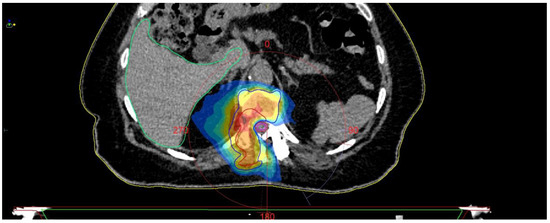

Fully Endoscopic Spine Separation Surgery in Metastatic Disease—Case Series, Technical Notes, and Preliminary Findings